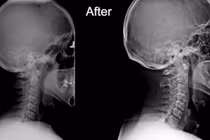

(khoahocdoisong.vn) - Mất đường cong sinh lý cổ gây tăng áp lực lên các đĩa đệm đốt sống cổ không chỉ gây thoái hóa hoặc thoát vị đĩa đệm mà còn giảm máu lưu thông lên não gây nhiều bệnh lý khó lường.